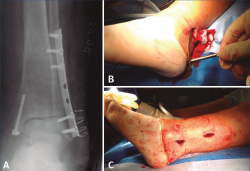

Clavo intramedular de peroné

Las ventajas descritas en el tornillo intramedular de peroné son aplicables al clavo intramedular de peroné. Varios estudios describen estas ventajas del uso del clavo intramedular de peroné en el paciente anciano, en cuanto a menor agresión de las partes blandas, mayor respeto de la biología ósea, menor prominencia de material y sobre todo menor tasa de complicaciones de partes blandas, como dehiscencias o infecciones, en comparación con la osteosíntesis convencional(12,18,54,57,58). Algunos autores llegan a considerarlo el tratamiento de elección en pacientes con problemas de partes blandas previos a la cirugía o con alto riesgo de complicaciones(57).

Jordan(12) realiza una revisión sistemática donde incluye 10 estudios con 711 fracturas inestables de tobillo tratadas con clavo intramedular de peroné y concluye que no hay diferencias en el resultado funcional final pero sí menores complicaciones que con la osteosíntesis convencional. Debe resaltarse que en 7 de los estudios incluidos en esta revisión autorizaban al menos la carga parcial y en 2 de ellos la carga completa dependiendo del patrón de fractura(12).

White(18) publica un ensayo clínico aleatorizado con 100 pacientes mayores de 65 años con fractura de tobillo inestable, comparando el clavo intramedular con la osteosíntesis convencional, autorizando la carga protegida según la tolerancia en ambos grupos. No encuentra diferencias significativas en el resultado funcional pero sí en las complicaciones de partes blandas (16% de infecciones en el grupo convencional versus 0% con el clavo). En ambos grupos presenta pacientes con necesidad de retirada de material (12% en el grupo convencional y 10% en el grupo del clavo, siendo en este último grupo solo la retirada de algún tornillo de bloqueo). El autor refiere que, aunque el coste del implante es mayor, el coste global fue inferior en el grupo del clavo al sumar el coste del tratamiento de las complicaciones. También señala la ventaja de no demorar la cirugía por inflamación y un tiempo quirúrgico menor en el grupo del clavo(18).

Una de las principales limitaciones que tenían estos clavos en sus primeros diseños eran la migración del implante y el acortamiento del peroné; sin embargo, con los nuevos implantes con bloqueos proximales y distales, estos problemas han disminuido y nos han permitido ampliar sus indicaciones, como en las fracturas conminutas, permitiendo mantener la longitud del peroné y evitando su acortamiento(54,57,58). Además, los nuevos clavos presentan la opción de estabilizar lesiones asociadas de la sindesmosis(18,58).

Estudios biomecánicos en cadáver han demostrado superioridad de los nuevos clavos en la resistencia a la torsión en comparación con la osteosíntesis convencional (placa tercio de caña y tornillo interfragmentario) en fracturas transindesmales con hueso osteoporótico(59). Sin embargo, en comparación con las nuevas placas bloqueadas, un estudio biomecánico demuestra que los clavos presentan menor resistencia a la torsión en fracturas simuladas de tipo Weber C conminutas, pero sin diferencias en la diastasis de la sindesmosis, y presentando similares características de fallo en ambos implantes(60).

Como consideración técnica, Bugler(58) en su serie presenta complicaciones de acortamiento y subluxación lateral en algunos casos iniciales sin bloqueo del clavo o solo el bloqueo distal. Recomienda el doble bloqueo con un tornillo proximal transindesmal (independientemente de si existe o no lesión de la sindesmosis) y un tornillo distal anteroposterior, para aumentar la estabilidad y mantener la longitud, no presentando las complicaciones previas con esta modificación técnica y con buenos resultados radiológicos y clínicos.